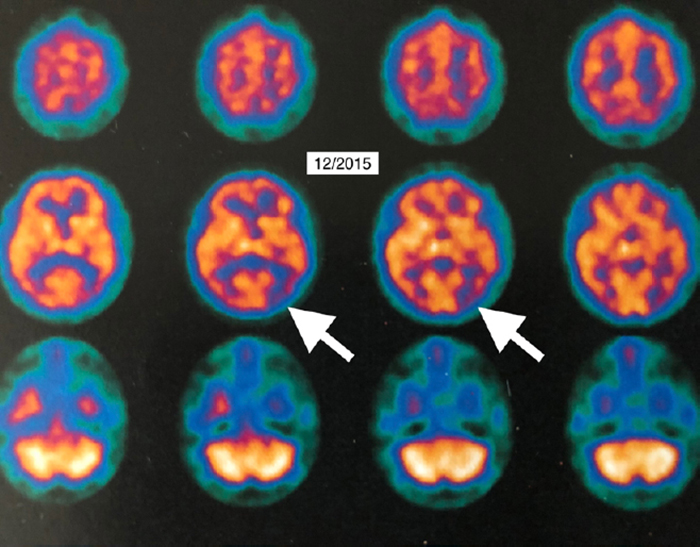

The authors report the case of a 58-year-old female who had experienced five years of cognitive decline, which began accelerating rapidly. Single photon emission computed tomography (SPECT) suggested Alzheimer’s disease. The diagnosis was confirmed by 18Fluorodeoxyglucose (18FDG) positron emission tomography (PET) brain imaging, which revealed global and typical metabolic deficits in Alzheimer’s.

The report also contains video imaging, including unique rotating PET 3D Surface Reconstructions, which allow the lay person to easily see the improvements in brain function.